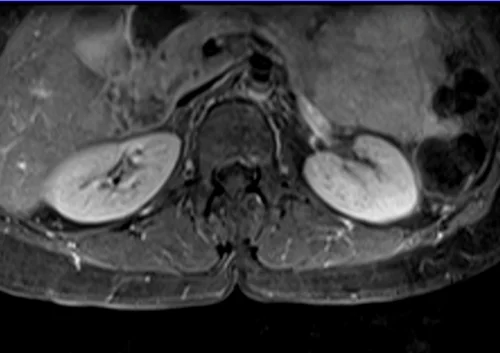

L plexus mri T1 fat saturated post contrast axial images